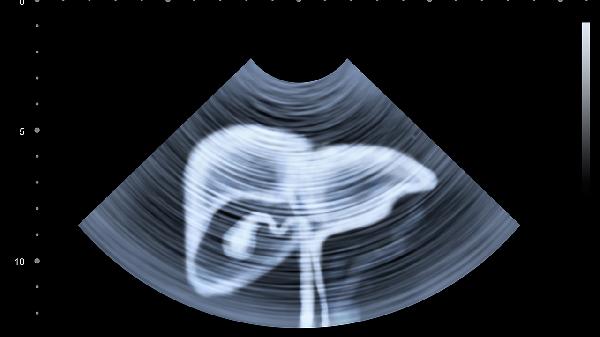

乙肝患者每3-6个月要做一次甲胎蛋白和肝脏超声检查。普通人每年也应做肝功能检查。